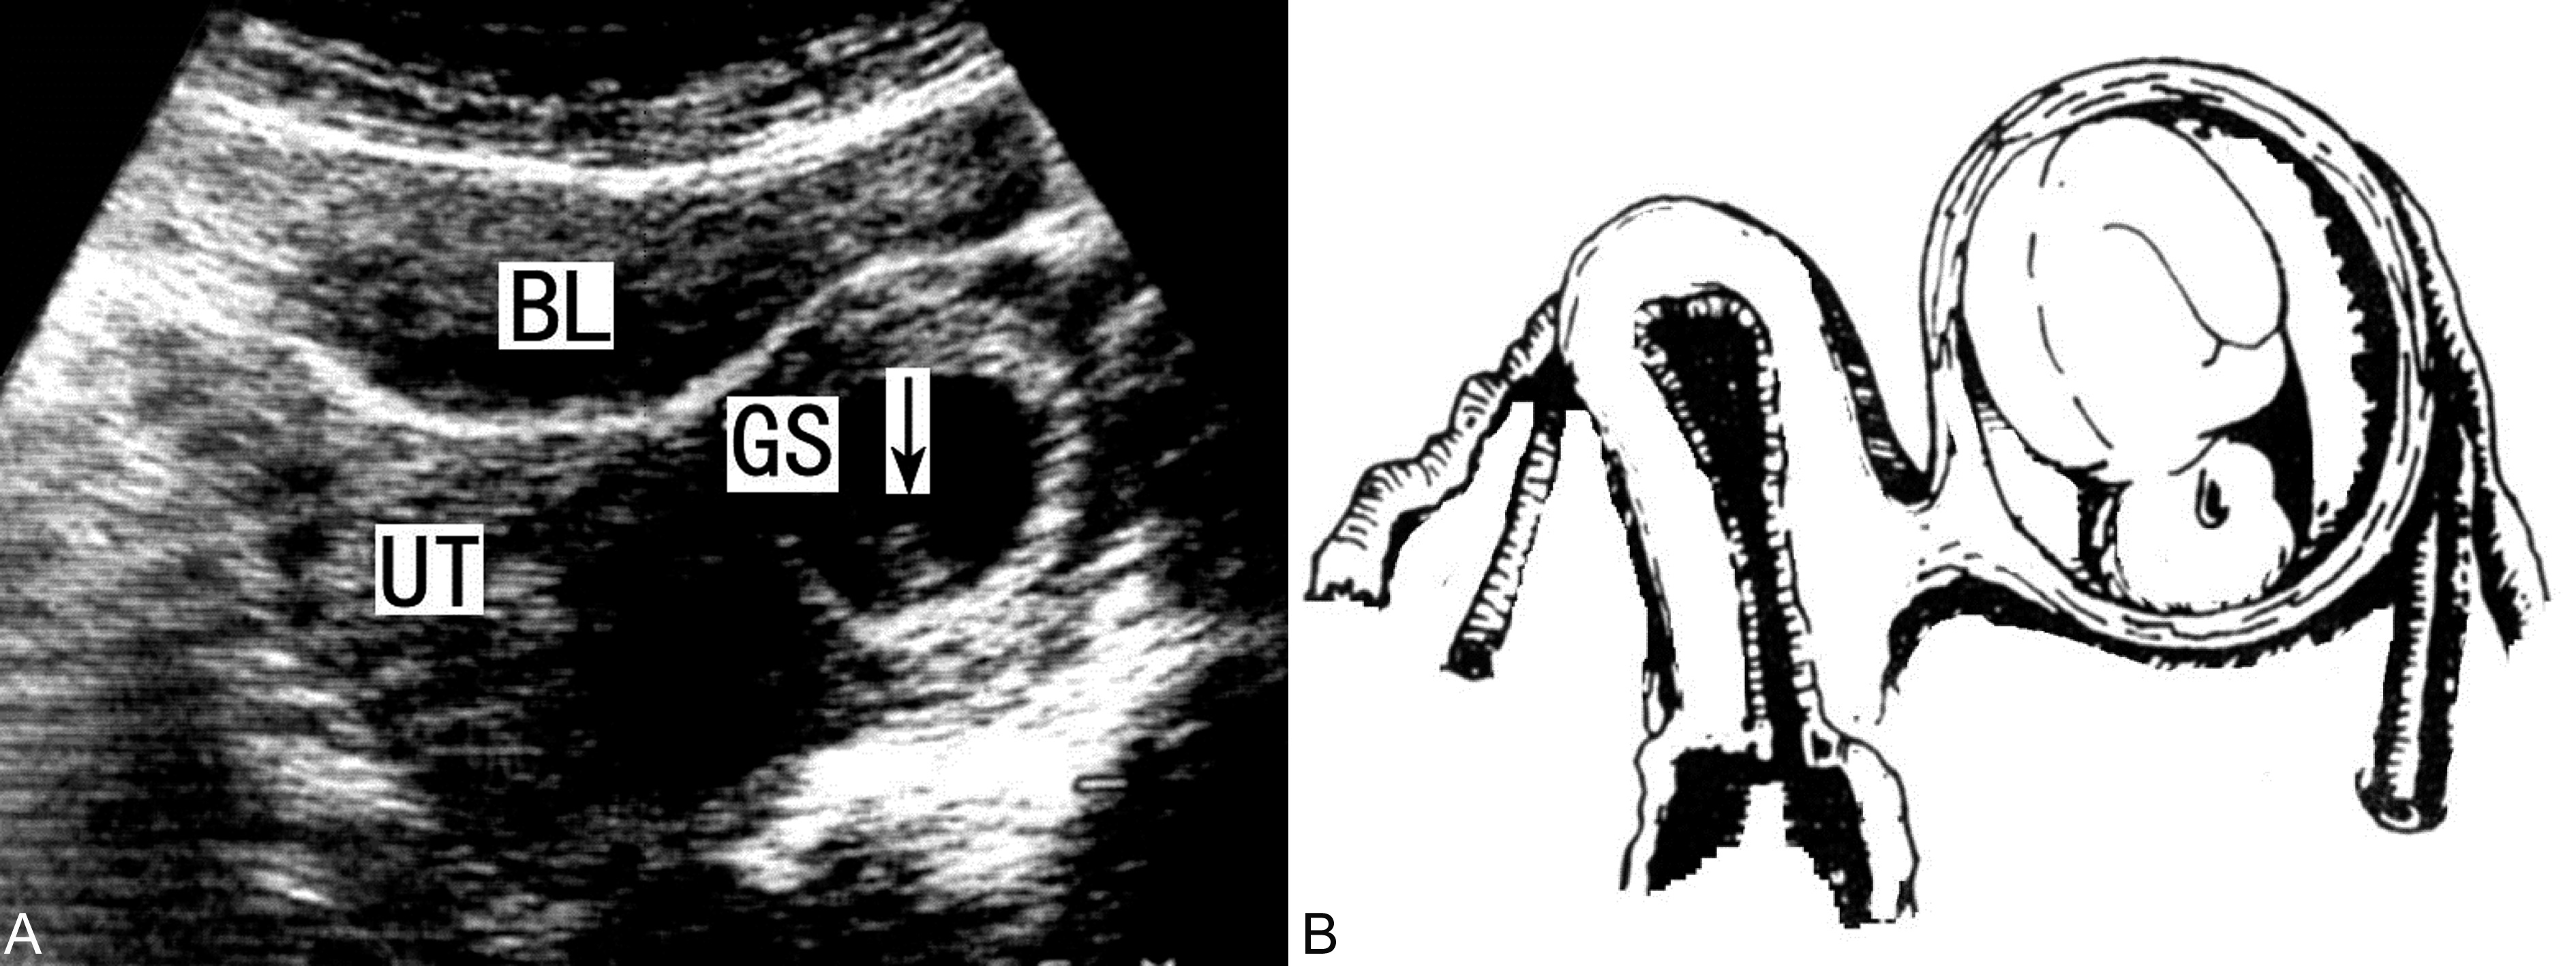

在妊娠早期,残角子宫未破裂前,超声显像检查可以发现一个相对较小的子宫和宫旁的异常回声,与输卵管妊娠相似,可以显示单角子宫内假孕囊回声和对侧形态正常的妊娠囊和胚胎回声,仔细检查可以在妊娠囊周围显示较厚的肌肉组织,相对独立(图1),与对侧子宫有稍强的间隔回声,并且不能发现同侧的子宫颈而与双子宫不同,同侧卵巢可以显示且回声基本正常。结合临床检查资料可以做出子宫残角妊娠的诊断。此点也可能是子宫残角妊娠与输卵管妊娠和双角子宫妊娠的鉴别要点。

图1子宫残角妊娠声像图(A)及其示意图(B)

子宫残角妊娠破裂后可以显示与输卵管妊娠相似的回声图像,在子宫旁显示由妊娠产物和出血形成的团块状回声,体积多数较大,出血量常较多,但很少能够显示残存的肌壁回声。如果能够发现肌壁回声,则应首先考虑为子宫残角妊娠破裂。但多数情况下超声显像检查很难将破裂的子宫残角妊娠与破裂的输卵管妊娠鉴别。